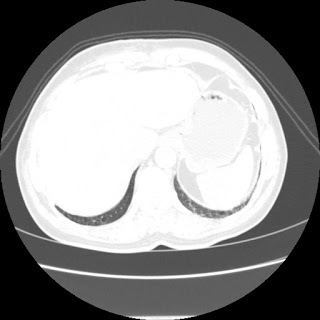

A 62 years old man with enlarged mole on chest since 2 months.

CT chest :-